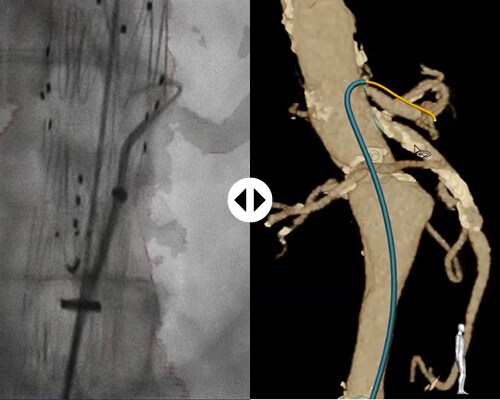

With FORS technology, clinicians can carry out parts of minimally-invasive interventions without the need for X- ray, which should minimize the risks associated with long-term radiation exposure.

X-ray is still necessary to visualize the patient anatomy. FORS technology only visualizes devices. However, FORS has already been shown to reduce radiation exposure, for the patient and staff, during complex aortic procedures.